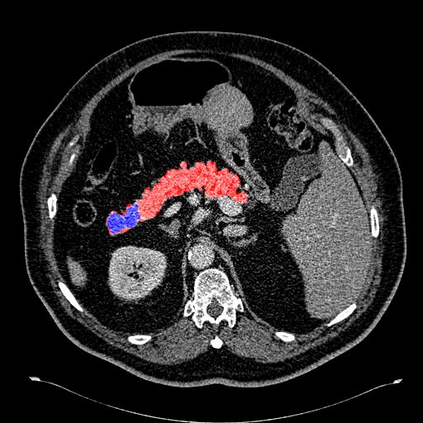

In this paper, we adopt 3D Convolutional Neural Networks to segment volumetric medical images. Although deep neural networks have been proven to be very effective on many 2D vision tasks, it is still challenging to apply them to 3D tasks due to the limited amount of annotated 3D data and limited computational resources. We propose a novel 3D-based coarse-to-fine framework to effectively and efficiently tackle these challenges. The proposed 3D-based framework outperforms the 2D counterpart to a large margin since it can leverage the rich spatial infor- mation along all three axes. We conduct experiments on two datasets which include healthy and pathological pancreases respectively, and achieve the current state-of-the-art in terms of Dice-S{\o}rensen Coefficient (DSC). On the NIH pancreas segmentation dataset, we outperform the previous best by an average of over 2%, and the worst case is improved by 7% to reach almost 70%, which indicates the reliability of our framework in clinical applications.